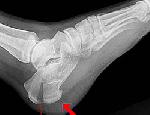

Переломы пяточной кости составляют около 4 % от общего числа переломов. Практически всегда возникают в результате падения с высоты в положении стоя вследствие удара пятками о землю. Часто сочетаются с переломами поясничных и грудных позвонков, переломами и переломовывихами лодыжек. В 15% случаев наблюдаются двухсторонние переломы пяточных костей. Симптомы перелома пяточной кости включают боли и отечность пяточной области, расширение и уплощение пятки, невозможность оперы на пятку при сохранности объема движений голеностопного сустава. Диагностика перелома пяточной кости производится травматологом по данным рентгенографии стопы в 3-х проекциях. Лечение включает наложение гипсовой лонгеты от пальцев до колена, затем проведение ЛФК и массажа.

- Рентгенография. Исследование осуществляется в двух проекциях. Рассматривают таранную, медиальную и латеральную кости.